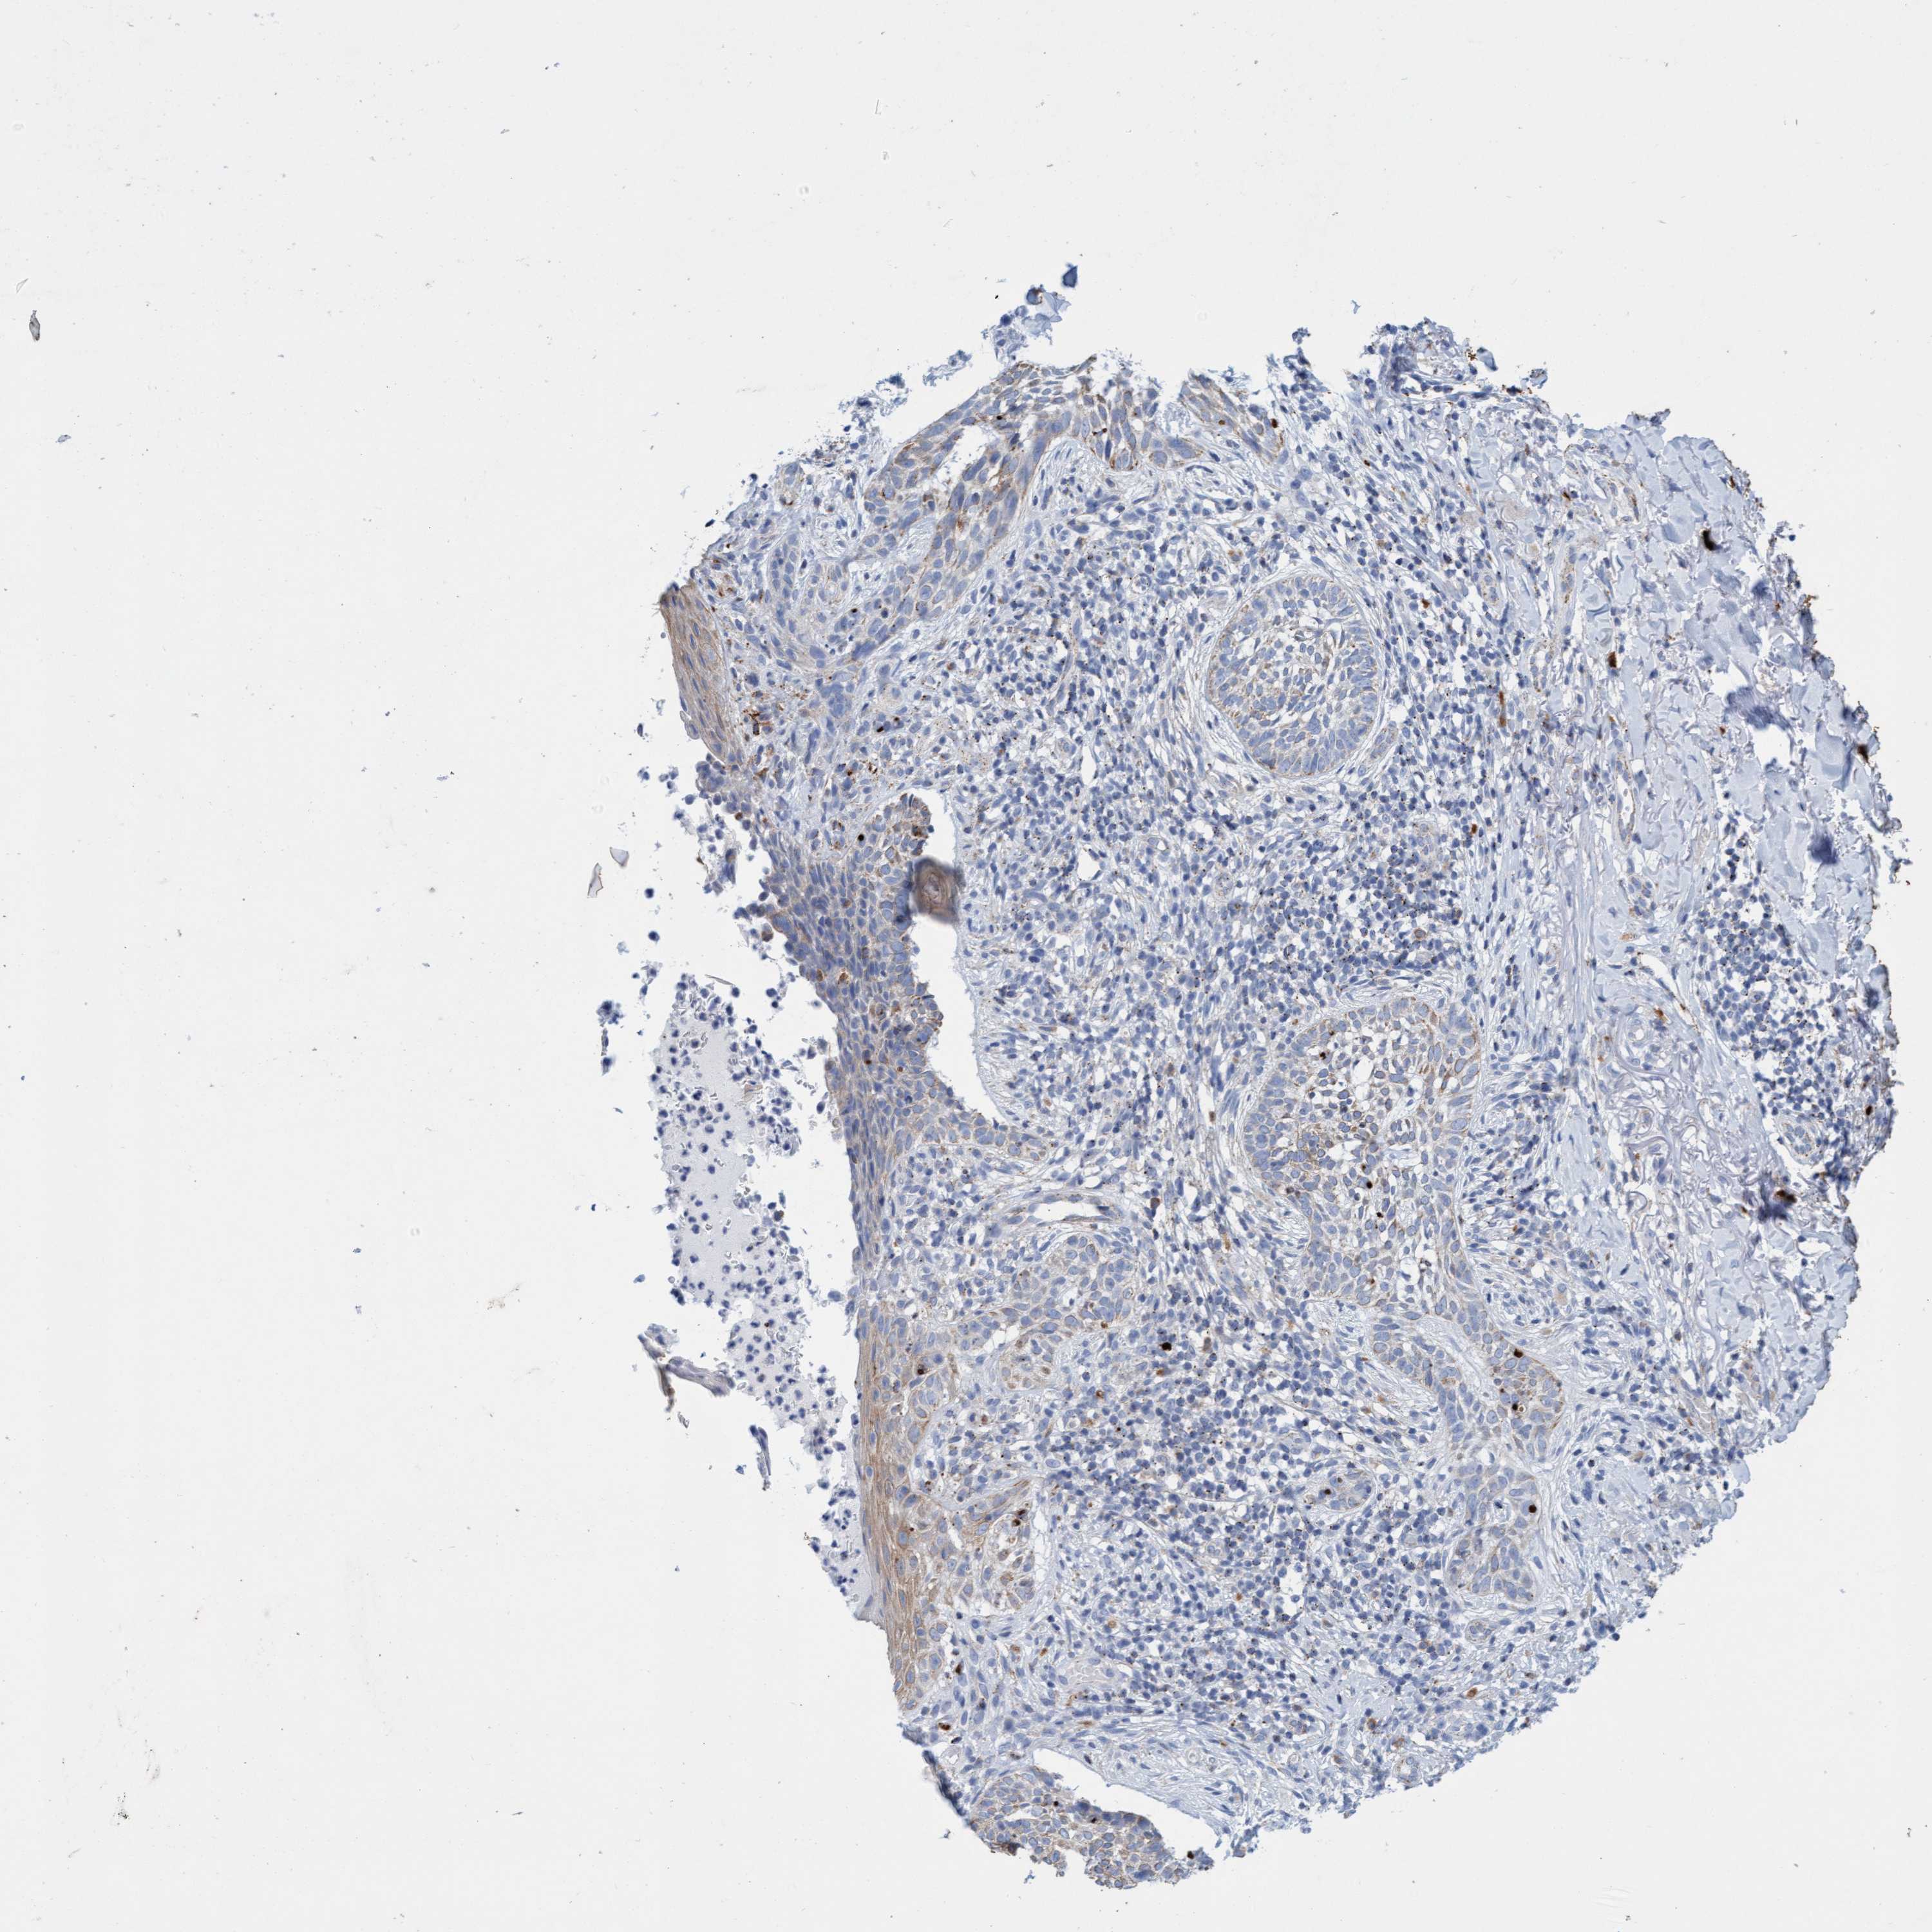

SKIN CANCER - Protein expressioni

A mouse-over function shows sample information and annotation data. Click on an image to view it in a full screen mode. Samples can be filtered based on level of antibody staining by selecting one or several of the following categories: high, medium, low and not detected. The assay and annotation is described here.

Antibody stainingi

Antibody staining in the annotated cell types in the current human tissue is reported as not detected, low, medium, or high, based on conventional immunohistochemistry profiling in selected tissues. This score is based on the combination of the staining intensity and fraction of stained cells.

Each image is clickable and will lead to virtual microscopy that enables deeper exploration of all samples and also displays staining intensity scores, fraction scores and subcellular localization as well as patient and tissue information for each sample.

Antibody HPA023436

Basal cell carcinoma

Squamous cell carcinoma, NOS

Squamous cell carcinoma, metastatic, NOS